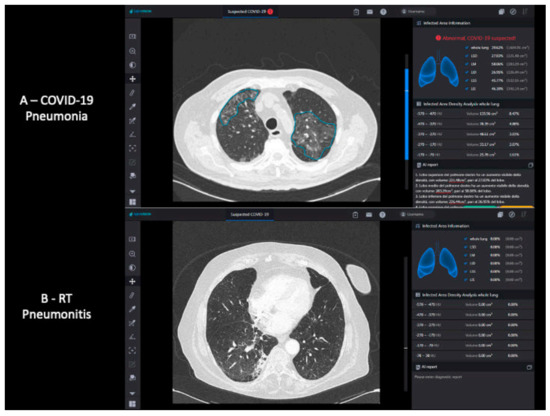

2.3. Deep Learning Algorithm Analysis

- Mallio, C.A.; Napolitano, A.; Castiello, G.; Giordano, F.M.; D’Alessio, P.; Iozzino, M.; Sun, Y.; Angeletti, S.; Russano, M.; Santini, D.; et al. Deep Learning Algorithm Trained with COVID-19 Pneumonia Also Identifies Immune Checkpoint Inhibitor Therapy-Related Pneumonitis. Cancers 2021, 13, 652. [Google Scholar] [CrossRef]